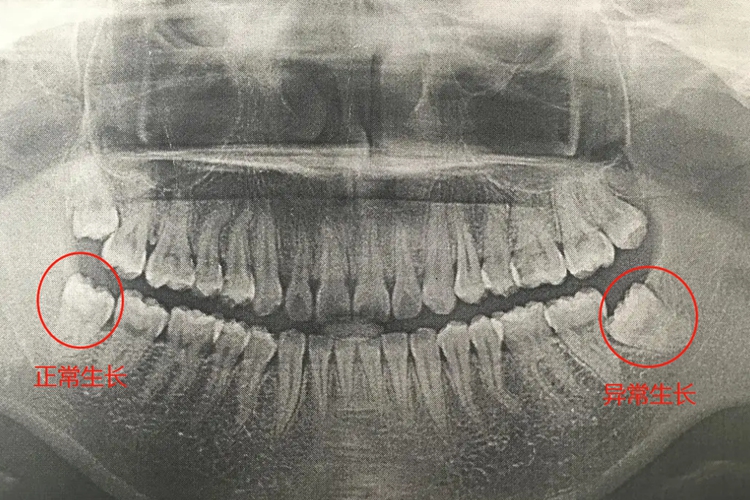

智齿的正常生长方向应与其他牙齿呈平行状态,没有成角趋势,不会挤压邻近牙齿,顺利萌出,没有中途停滞的情况。

智齿通常生长较为缓慢,十几岁左右甚至更晚才会萌出。正常生长的智齿方向不会挤压邻近牙齿,没有成角趋势,呈平行状态,从而也就不会出现相应的异常症状。

绝大多数情况下智齿并不能顺利正常生长,进而会发生阻生智齿的情况。如果智齿萌出不全或者发生阻生,就可能会导致牙冠周围的软组织发生炎症,出现智齿冠周炎。还有可能会影响邻牙的健康。通常可出现牙齿疼痛、口臭、局部牙龈红肿与溃烂等情况,此时需要及时拔除智齿,以防进一步生长影响其他牙齿的健康。